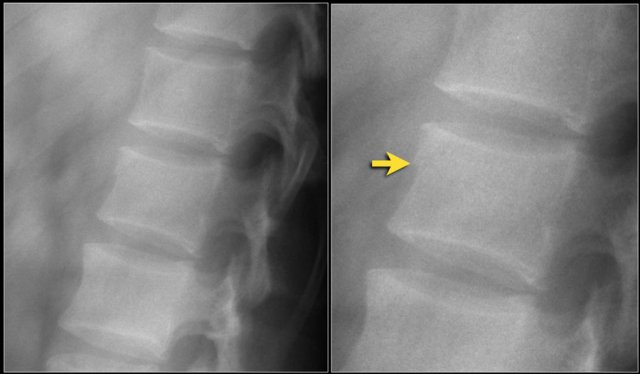

Here's another example.

You could call these compression fractures.

There is loss of height with a dense band of impaction and there is an anterosuperior corner fracture on both levels.

But look at the spinous processes.

One of the spinous processes is in two pieces and the two pieces are widely separated.

So this is a distraction fracture, also known as Chance fracture.

Now when you describe such a fracture the first word in your report should be distraction, i.e. morphology: 4 points.